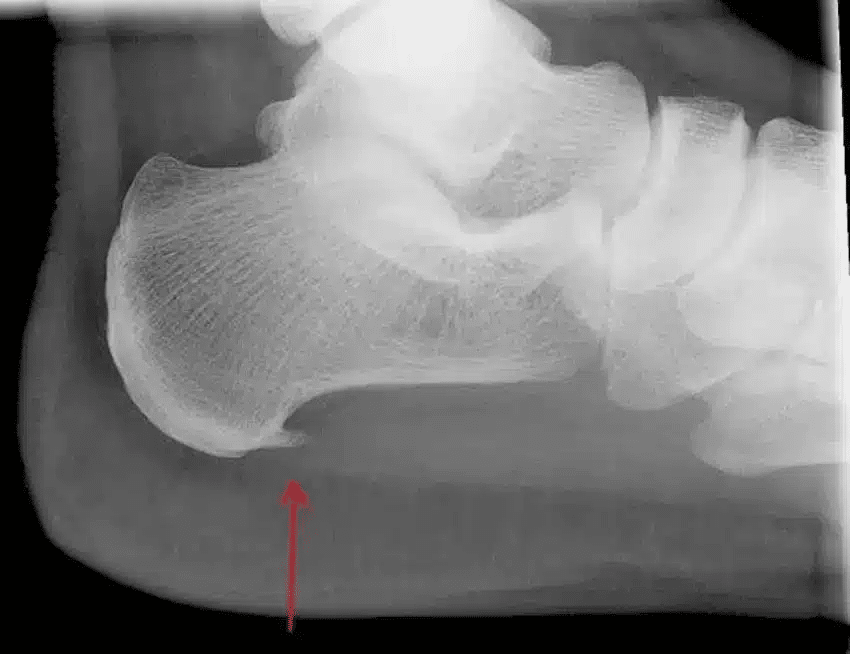

Op de foto hieronder zie je dat er een extra stukje bot bij de pijl is gegroeid. Dit kan een oorzaak zijn van de ontsteking van de pees die op dezelfde plek zit. Dit extra stukje bot kunnen wij goed zien op een echo.

Door gerichte druk uit te oefenen op de peesplaat kan worden beoordeeld of dit pijn veroorzaakt. Als deze druk pijn veroorzaakt, kan dit duiden op hielspoor. Bij Evolution Fysiotherapie maken we ook gebruik van echografie, een pijnloze techniek waarmee we de peesplaat door de huid heen kunnen bekijken.

Met echografie kunnen we hielspoor zichtbaar maken en zelfs de voortgang meten. Als er een extra stukje bot op de hiel is gegroeid, zien we dit ook direct.